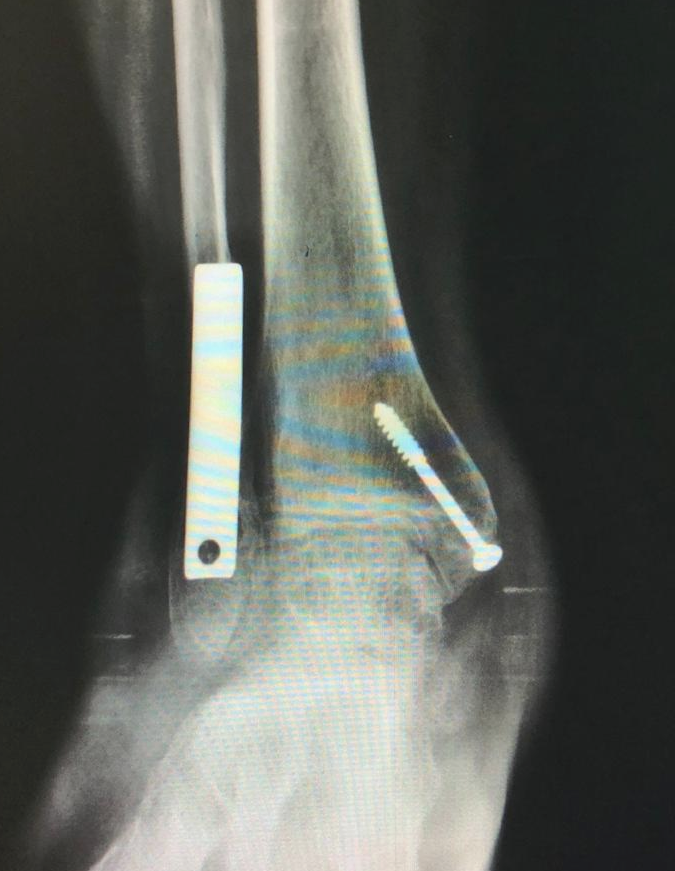

Artroplastia Total do Tornozelo

Cirurgia de substituição articular para tratamento da Osteoartrose do Tornozelo